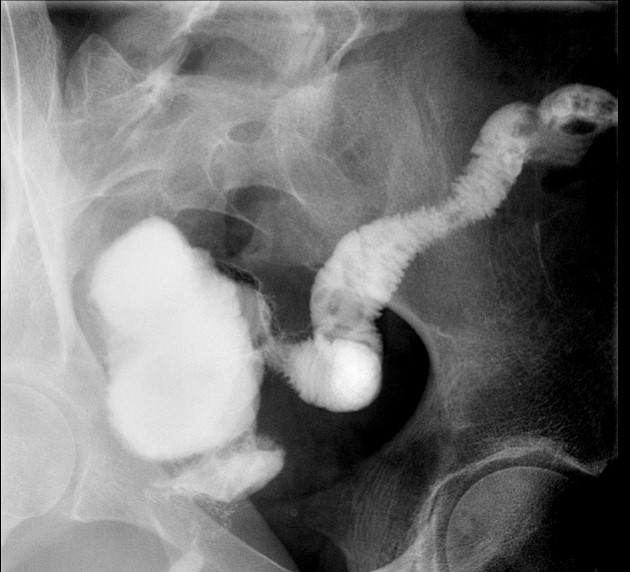

- The technologist will obtain a scout image. Assess the image for any possible contraindications such as pneumoperitoneum, evidence of ileus or obstruction, or residual contrast material

(key image 1).